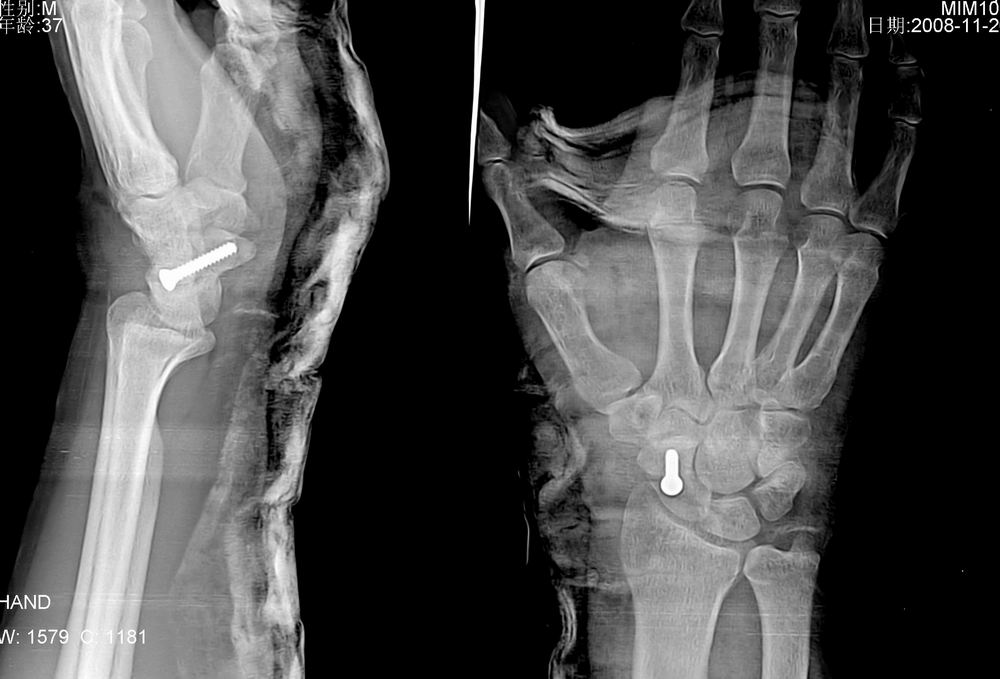

标题: X5107 :舟骨骨折

病人来的时候由于韧带砍断了,体位不正,在接韧带时发现舟骨有骨折,做了手术。

术后片如下: